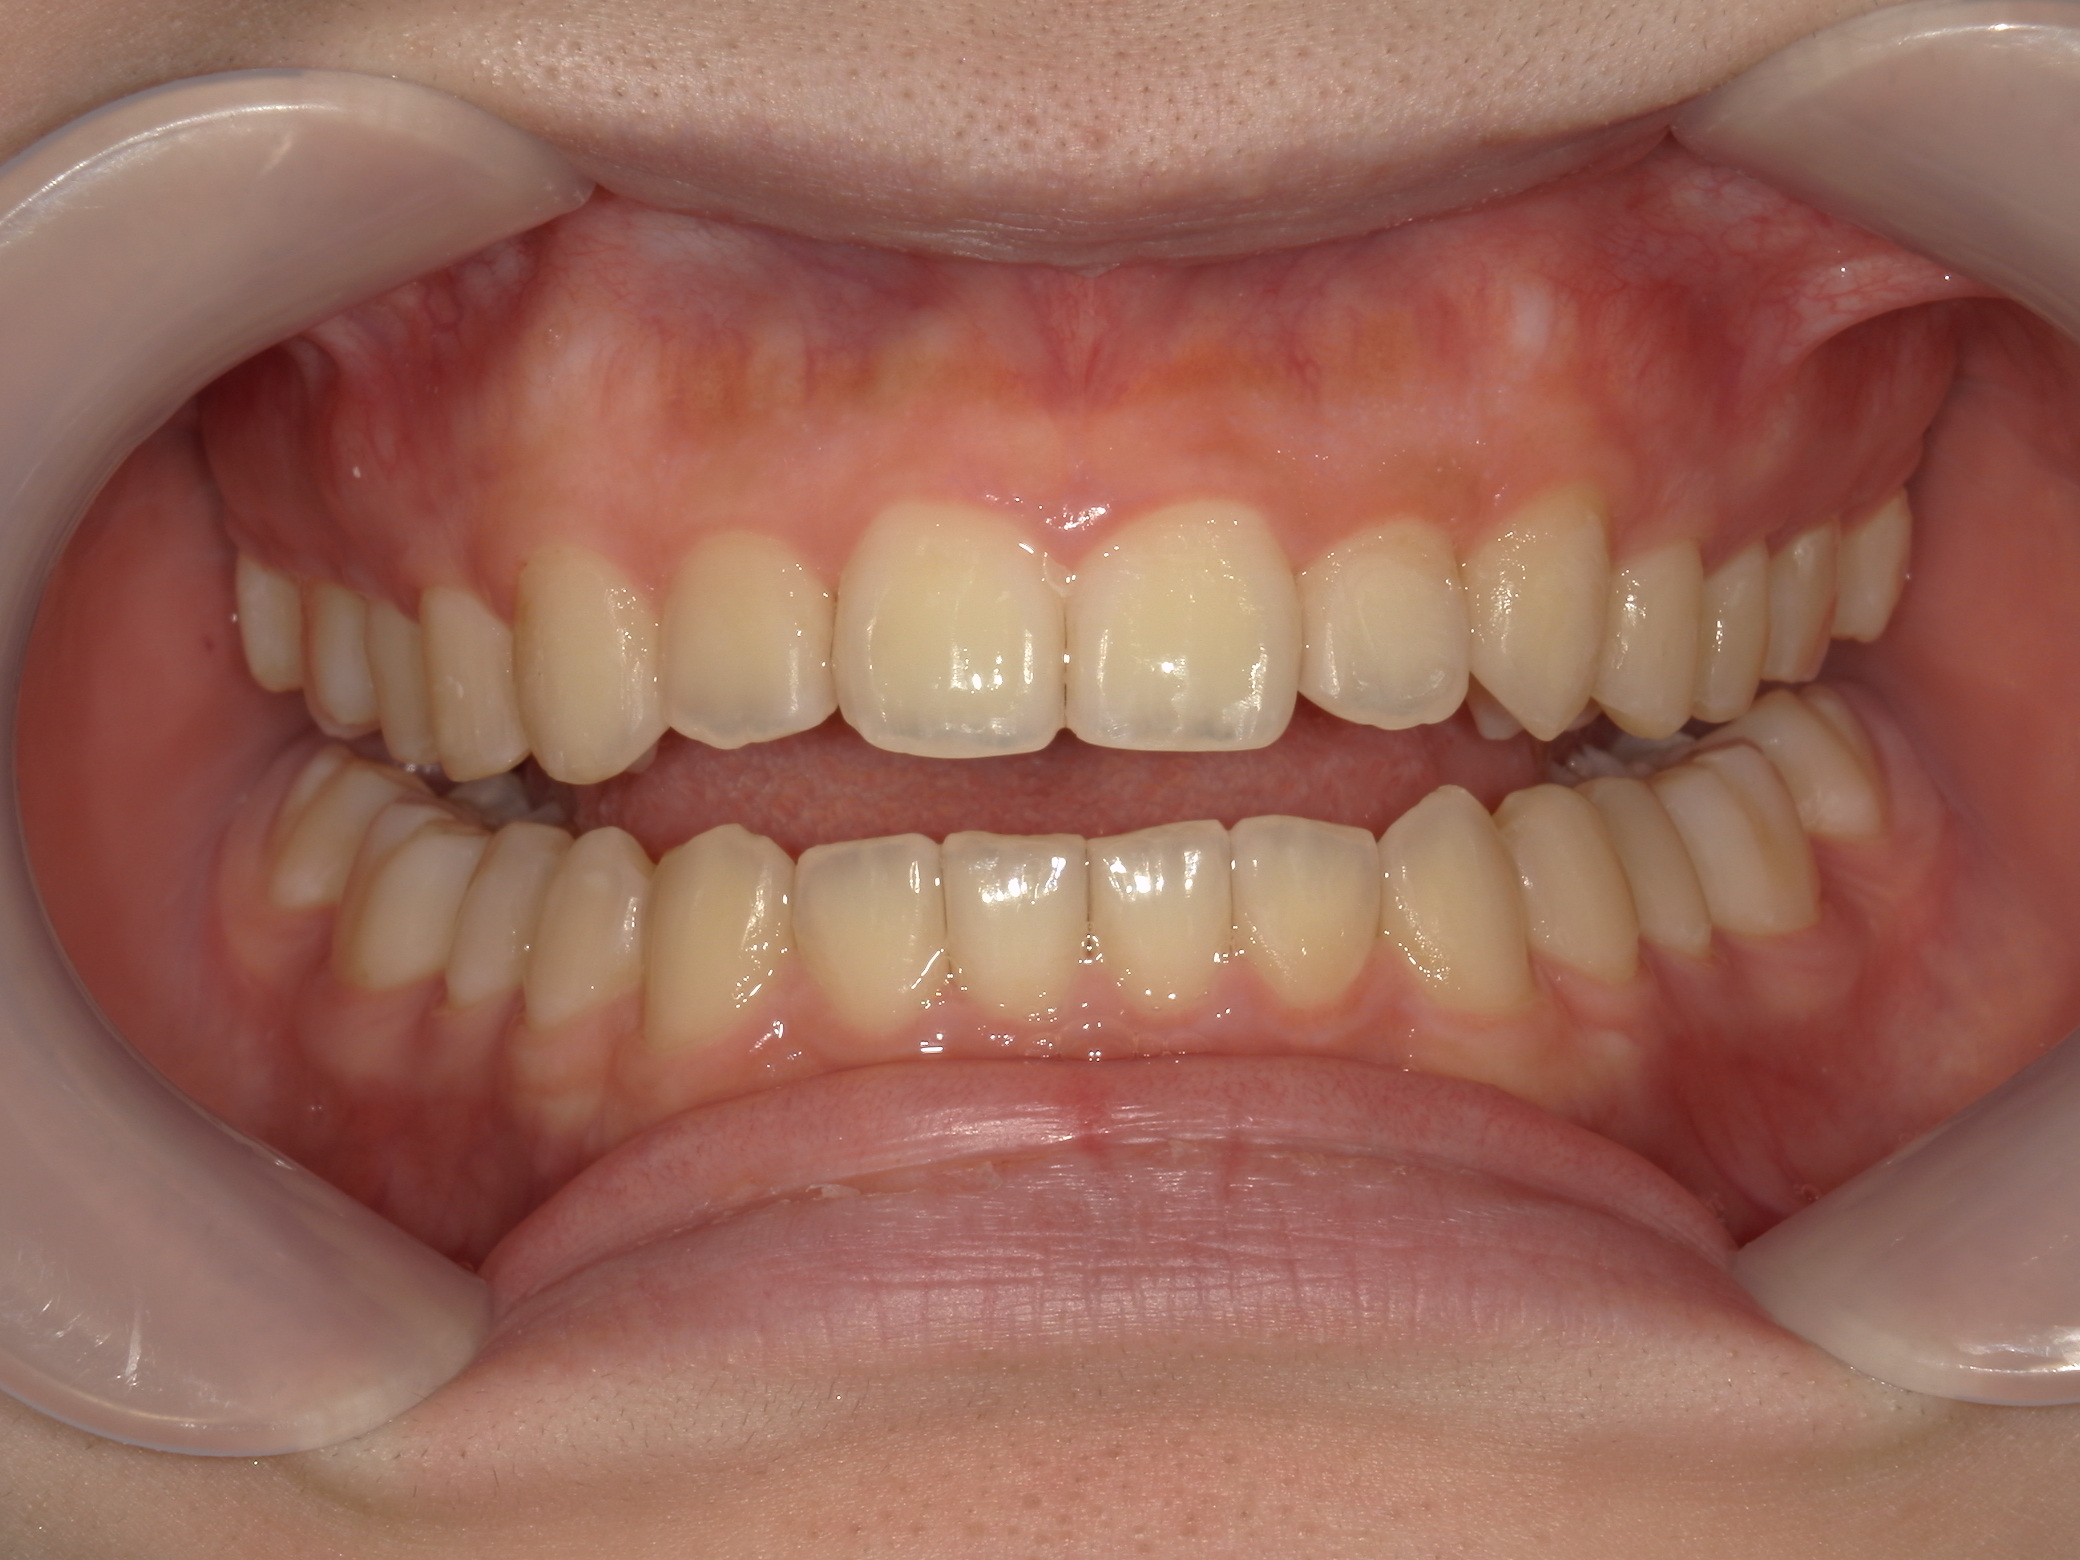

インビザライン矯正 症例(19)

主訴: 左上犬歯が出ているのが気になる

| 治療期間 | 4年5ヶ月 |